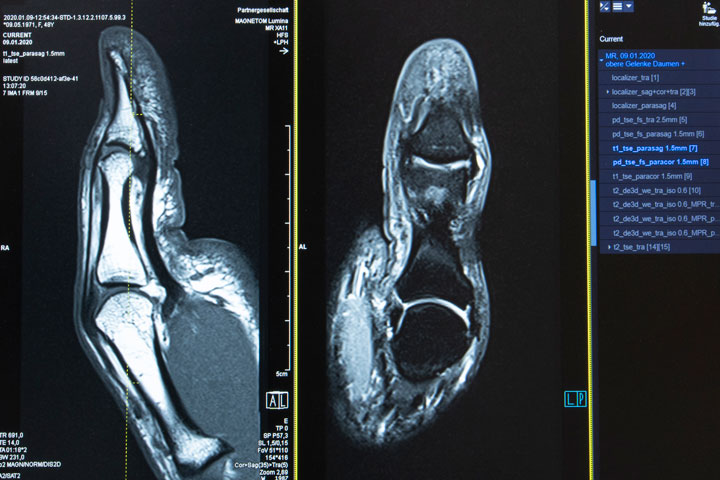

Magnetresonanztomographie (MRT)

Wichtigste Voraussetzung für das Erkennen eines krankhaften Befundes ist eine optimale Bildqualität. Nur so gelingt es auch kleinste Veränderungen, die Beschwerden verursachen (z.B. kleiner Bandscheibensequester, der auf den Nerv drückt) zu diagnostizieren und damit entsprechend korrekt zu behandeln.

Für diese hochauflösende Bildqualität verwenden wir mehrere Komponenten

- 3.0 Tesla Hochfeld-Magnetresonanztomograph SKYRA (48-Kanal), durch die hohe Feldstärke sind auch kleinste Strukturen darzustellen.

- Mehrkanal-Spulensysteme, speziell konstruiert für die einzelnen Organe: (16-Kanal Handgelenk, 16-Kanal Schulter, 15-Kanal Knie-Sprunggelenk, 18-Kanal Brust, 18-Kanal Bauch/Becken) für eine optimale Bildqualität.

- Spezielle Sequenzen (Aufnahmeprotokolle), individuell abgestimmt auf die Beschwerdesymptomatik und Fragestellung, die sich durch eine besonders dünne Schichtdicke und hohe Detailerkennbarkeit auszeichnen